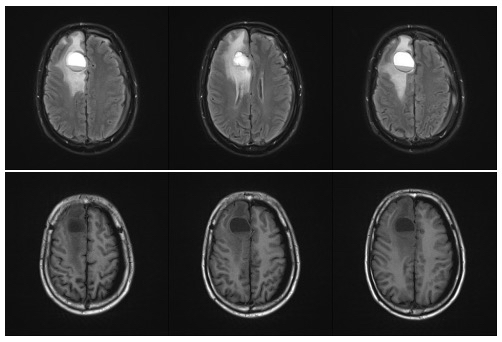

为了弄清病灶的“真面目”,县医院立刻安排了颅脑磁共振(MR)平扫及增强检查。影像画面清晰地显示,右侧额叶的病变范围不小,呈囊性改变,周围还存在典型的血管源性水肿带——所有迹象都指向一个令人担忧的方向:颅内恶性肿瘤的可能性很大。

术前核磁提示脑转移瘤

至此,一条完整的证据链逐渐成型:张先生难以忍受的头痛,根源是颅内高压;而颅内高压,源于额叶的占位病变;这个占位病变,极有可能是食管肿瘤转移而来,真正的“元凶”,就隐藏在食管里。经过系列手术后,困扰张先生多日的剧烈头痛显著缓解,颅内高压的警报暂时解除。